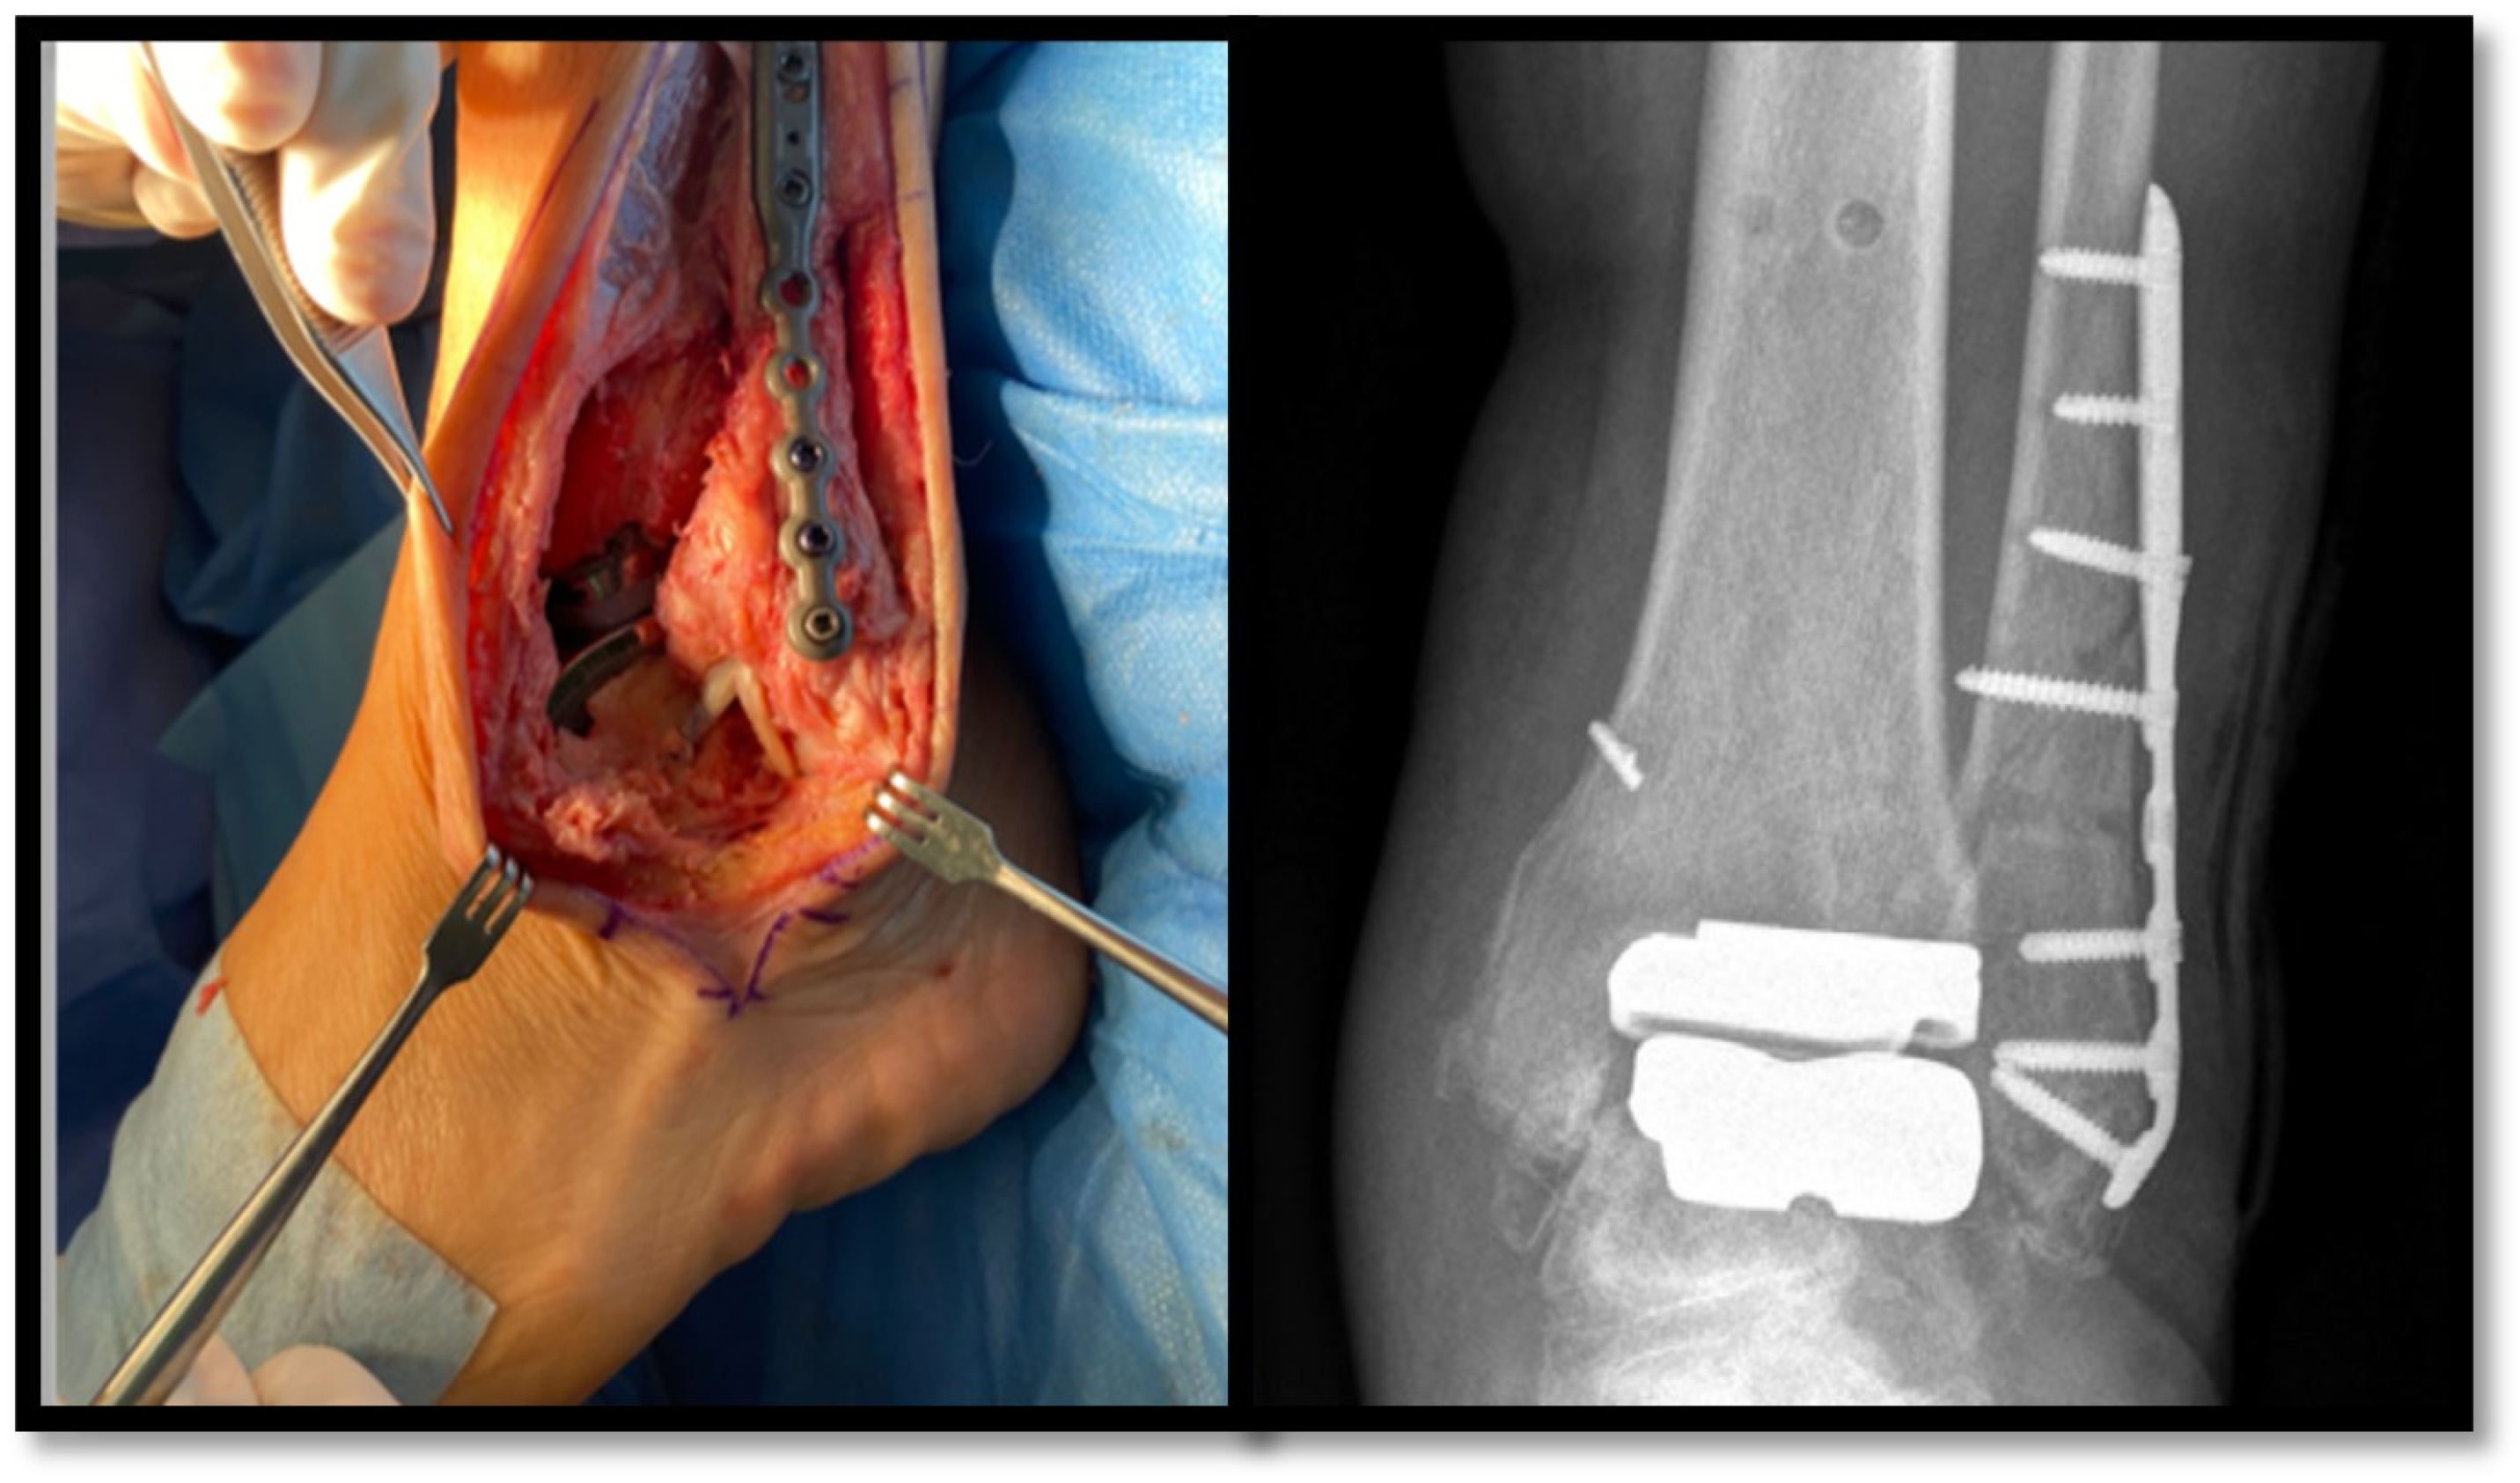

Ankle arthroplasty is increasingly being used for the treatment of ankle osteoarthritis [1]. In recent years, the transfibular approach has been shown to have functional advantages over the classic anterior incision, despite being more technically demanding and requiring the implantation of osteosynthesis material in the fibula (Figure 1) [2].

Figure 1. Transfibular approach in an ankle prosthetic implant. Surgical and radiological view. Adapted with permission from Ref. [2]. Copyright 2023, American College of Foot and Ankle Surgeons.